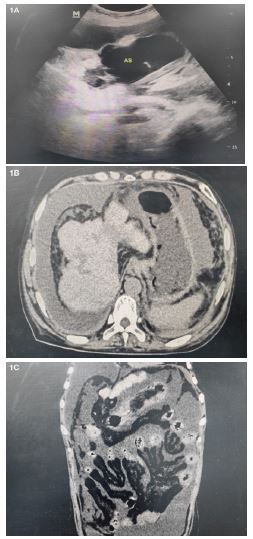

We present a 50-year-old woman hospitalized on November 9, 2023 with general abdominal pain worsened progressively of 9 days’ duration and ceftazidime was inefficacy. The patient’s medical history includes a six-year duration of autoimmune hepatitis with hepatocirrhosis, for which she has been regularly prescribed ursodeoxycholic acid capsules at a dosage of 250 mg three times daily. No history of glucocorticoid use and abdominal surgery. On admission, the patient presented with diffuse abdominal pain and weakness. The physical examination revealed afebrile status, blood pressure of 103/64 mmHg, pulse rate of 93 beats per minute, as well as diffuse abdominal rebound tenderness. No peripheral stigmata of infective endocarditis. B-ultrasonography showed a large amount of ascites, with floating objects presented in large grids (Figure 1a). Abdominal Computed Tomography (CT) studies demonstrated the peritoneum was thickened, the adipose space in the abdominal cavity was blurred, and the subcutaneous adipose layer on both abdominal walls was cloudy (Figure 1b & Figure 1c). The relevant laboratory data on admission were as follows: white blood cell 28.34E+09/L; neutrophil 26.56E+09/L; c-reactive protein 83.69 mg/dl; procalcitonin 11.59 ng/mL; lactic acid 7.41 mmo/L. The analysis revealed a leukocyte count of 3900E+06/μL with 80% neutrophils in the turbid abdominal effluent. The empirical therapy is initiated with meropenem (1g i.v. 8 hrly). The presence of E. avium was rapidly detected within 1 day using NGS. At once, linezolid was added to the meropenem anti-infection treatment regimen. It took 6 days for E. avium to be identified through culture-based methods. Antibiotic therapy consisting of meropenem (1g i.v. every 8 hours) and linezolid continued for 5 weeks, in conjunction with peritoneal lavage. The patient’s abdominal pain was alleviated, accompanied by a significant improvement in the clarity of the effluent. Then, the patient experienced an uneventful recovery and was discharged on day 36. Since her discharge from the hospital, she has been residing in her residence and remains ambulatory with crutches until February 1, 2024. (We have received written informed consent from the patient for publication of case details. We depersonalized data to disable the identification of the patient).